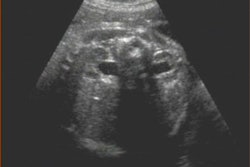

For fetuses 18 weeks' gestation or more, measurement of umbilical cord diameter was performed at a level less than 0.5 cm from the abdominal wall insertion. When the gestational age was between 14 and 18 weeks' gestation, a transverse section of cord was measured at the level of the wall insertion or at the level of the cord-free loop.

"Measurement calipers were placed at the outer edges of the umbilical cord to include umbilical cord vessels and the surrounding Wharton jelly," the authors wrote. Also, the number of umbilical cord vessels and amount of Wharton jelly was assessed. Ultrasound imaging was performed using a 6-MHz transabdominal transducer that had multiple frequency choice and harmonic capability for improved image quality.